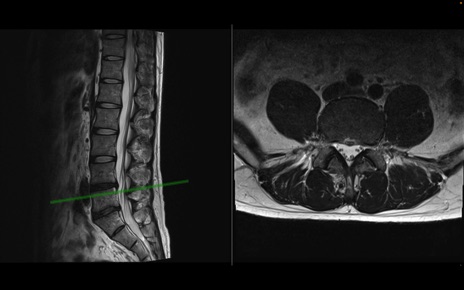

【症例】40歳代男性

【主訴】左臀部〜大腿後面痛み

【現病歴】2週間前から腰痛あり。2日前に夜中にくしゃみをした際に激痛が出現。疼痛強いため来院。

【身体所見】左臀部〜大腿後面、下腿後面のしびれ。SLR -/+ 30度、うつ伏せ困難、筋力低下なし。

異常所見と診断は?